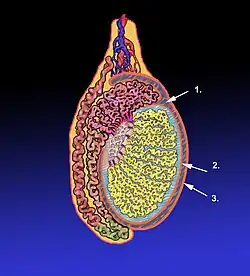

Diagram of a cross-section of a testicle. 1. Cavity of tunica vaginalis, 2. Visceral lamina, 3. Parietal lamina. | |